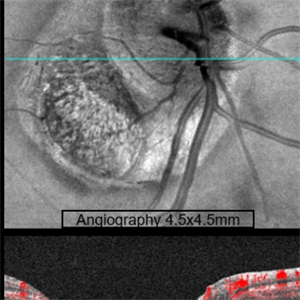

Coloboma of Optic Disc

Coloboma of Optic Disc

Sep 23 2022 by Kavya Rao, M.S

OCT and OCT Angiography (4.5x4.5mm)(ZEISS) of 39-year old man ,came for routine check up and diagnosed with coloboma of Optic Disc in the Right Eye as an incidental finding.

Photographer: Dr.KAVYA RAO, LIONS CLUB OF HYDERABAD, SADHURAM EYE HOSPITAL,HYDERABAD,INDIA

Condition/keywords: coloboma